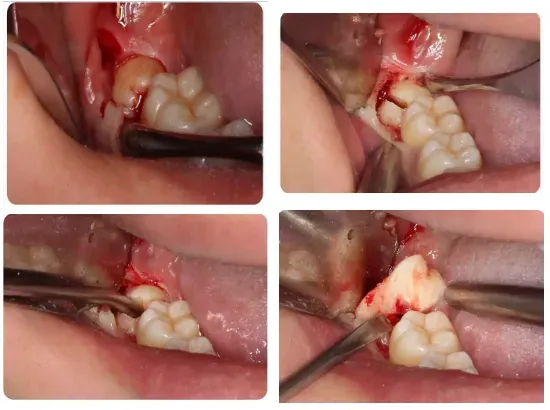

9、其他埋藏牙齿的阻力分析及手术设计;

上颌阻生第三磨牙的阻力分析及手术设计

通过病例讲解上颌阻生第三磨牙的微创拔除方法

通过病例讲解阻生尖牙、前磨牙、磨牙、多生牙的微创拔除方法